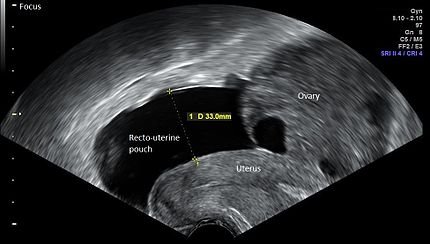

Clinical features include characteristics of Mild OHSS plus ultrasound evidence of abdominal fluid along with the increase in ovarian size up to 12 cm is there. Abdominal discomfort and gastrointestinal symptoms example nausea, vomiting and diarrhoea are frequent and more severe than mild OHSS. Blood tests will show haematocrit >41 %, WBC more than 15,000/microliter, lower Proteins.

Severe OHSS

In addition to the manifestations of moderate OHSS, severe OHSS is determined by the appearance of abdominal fluid with severe abdominal pain and some patients might have pleural effusion as well. Woman with severe  OHSS can gain weight between 15 to 20 kg within 5 to 10 days and exhibit progressive leucocytosis. Ascites and pleural effusion can affect lung function leading to lack of oxygen and breathlessness.

Diagnosis of  OHSS is by clinical history and ultrasound. Factors which can predict OHSS include :